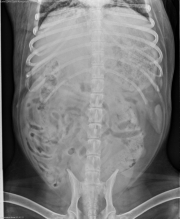

This week’s case is a 10 year old mixed breed dog with lethargy and inappetence. This case is challenging. See what you think of it and post in the comments.

VD Abdomen

In the thorax, there is a diffuse mixed pulmonary pattern with miliary nodular and bronchial components. There are also alveolar infiltrates in the ventral portion of the left cranial lung lobes, best noted on the right lateral projection. There is ill-defined soft tissue opacity dorsal to the carina, which may represent lymphadenopathy. The cardiovascular structures are within normal limits. Within the abdomen, the liver is enlarged, causing focal poor peritoneal detail.

Differential Diagnosis

• fungal pneumonia

• metastatic disease

• bronchoalveolar carcinoma

• hepatomegaly due to systemic or infiltrative disease

Disseminated coccidioidomycosis

This dog had a positive titre for coccidioidomycosis. Pulmonary infiltrates are often nodular but can appear diffuse. The ventral distribution of the alveolar component may indicate an additional secondary bacterial pneumonia. The hepatomegaly was presumed to be due to disseminated fungal infection.